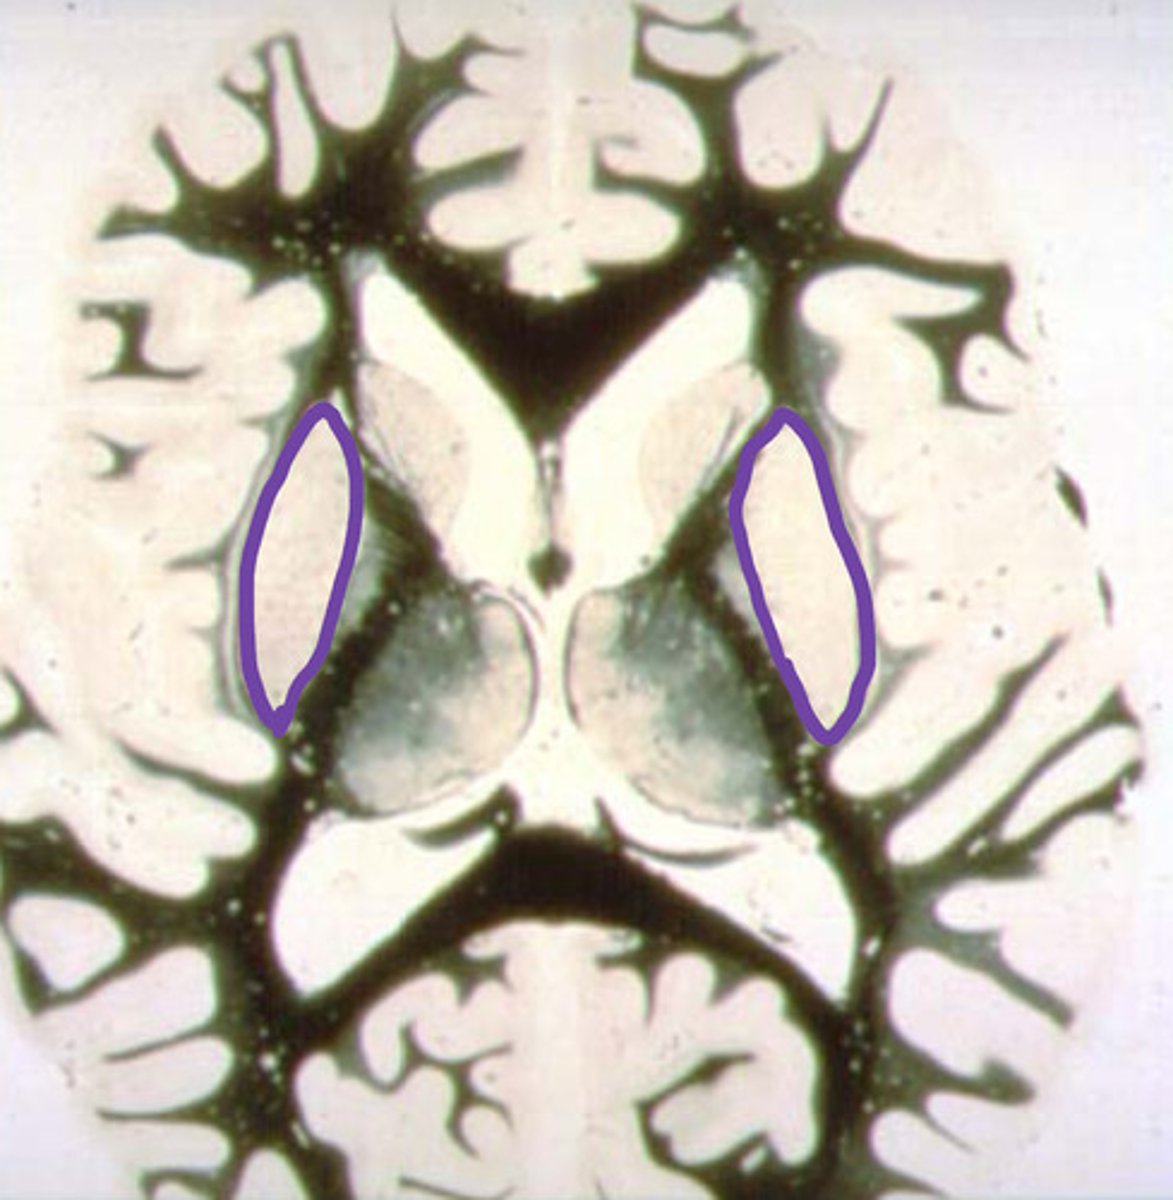

putamen

identify the structure

globus pallidus